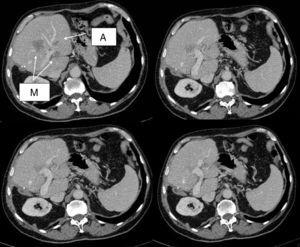

The patient is a 72-year-old male with a history of colon cancer and synchronous liver metastases that had been resected by means of right hepatectomy 14 months earlier. During follow-up, 3 new metastases were detected: 2 superficial lesions in segment II, and 1 deep lesion measuring 2cm in segment IV, which was in contact with the left portal vein and encompassed branches of this segment (Fig. 1). The location made surgical resection impossible. We considered the possibility of R0 treatment using combined surgery and radiofrequency ablation. In a multidisciplinary clinical session, treatment with 4 cycles of neoadjuvant FOLFIRI-cetuximab was decided. Re-evaluation with CT and MRI showed a partial response with no extrahepatic metastases.

The patient underwent surgery, involving individual non-anatomical resections of the metastases in segment II and radiofrequency ablation of the metastasis in segment IV. We used the Cool-tip™ RF Ablation System by Covidien with a needle whose radius of action was 3cm, and radiofrequency was applied with hilar clamping for 11min. The postoperative period was uneventful; transaminase levels were initially elevated (GOT/GPT=1505/1373IU/L; GGT/FA=241/128IU/L), then progressively descended, and liver function was normal. The patient was asymptomatic and discharged on the 7th day post-op. On the 12th day post-op, the patient was readmitted with fever. Lab workup showed normal liver function (GOT/GPT=59/161IU/L and GGT/FA=1213/726IU/L) and normal bilirubin. CT detected a collection that occupied the entire segment IV, with dense content and air bubbles and no arterial or venous contrast material (Fig. 2). Needle aspiration obtained a small amount of serosanguineous fluid that was sent for culture, which ruled out the presence of biliary content. Both this culture and the blood cultures were negative. The clinical-radiological diagnosis was complete ischemic necrosis of segment IV. The patient was treated with empirical antibiotics and antipyretics, after which he presented good clinical progress. The patient was discharged after 6 days with oral antibiotic therapy (the patient's residence was in another province, which made early discharge difficult). In spite of the complication described, the treatment was effective and there was no evidence of disease 6 months afterwards.